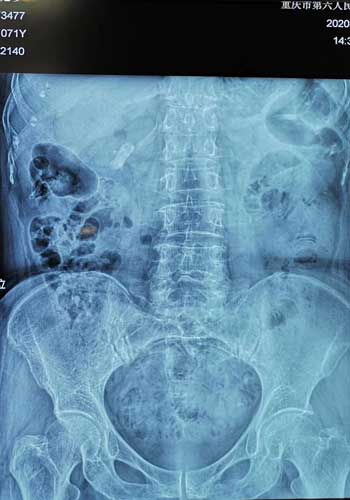

术后腹部平片患者膀胱内无结石残留。院方供图

7月21日,由靳文生主任主刀,在短短的一个多小时内,通过先进的EMS碎石技术,将患者膀胱内近似鹅蛋大小的结石顺利粉碎取出。术后患者尿频尿急症状得到了明显缓解,困扰患者已久的“难言之隐”迎刃而解。